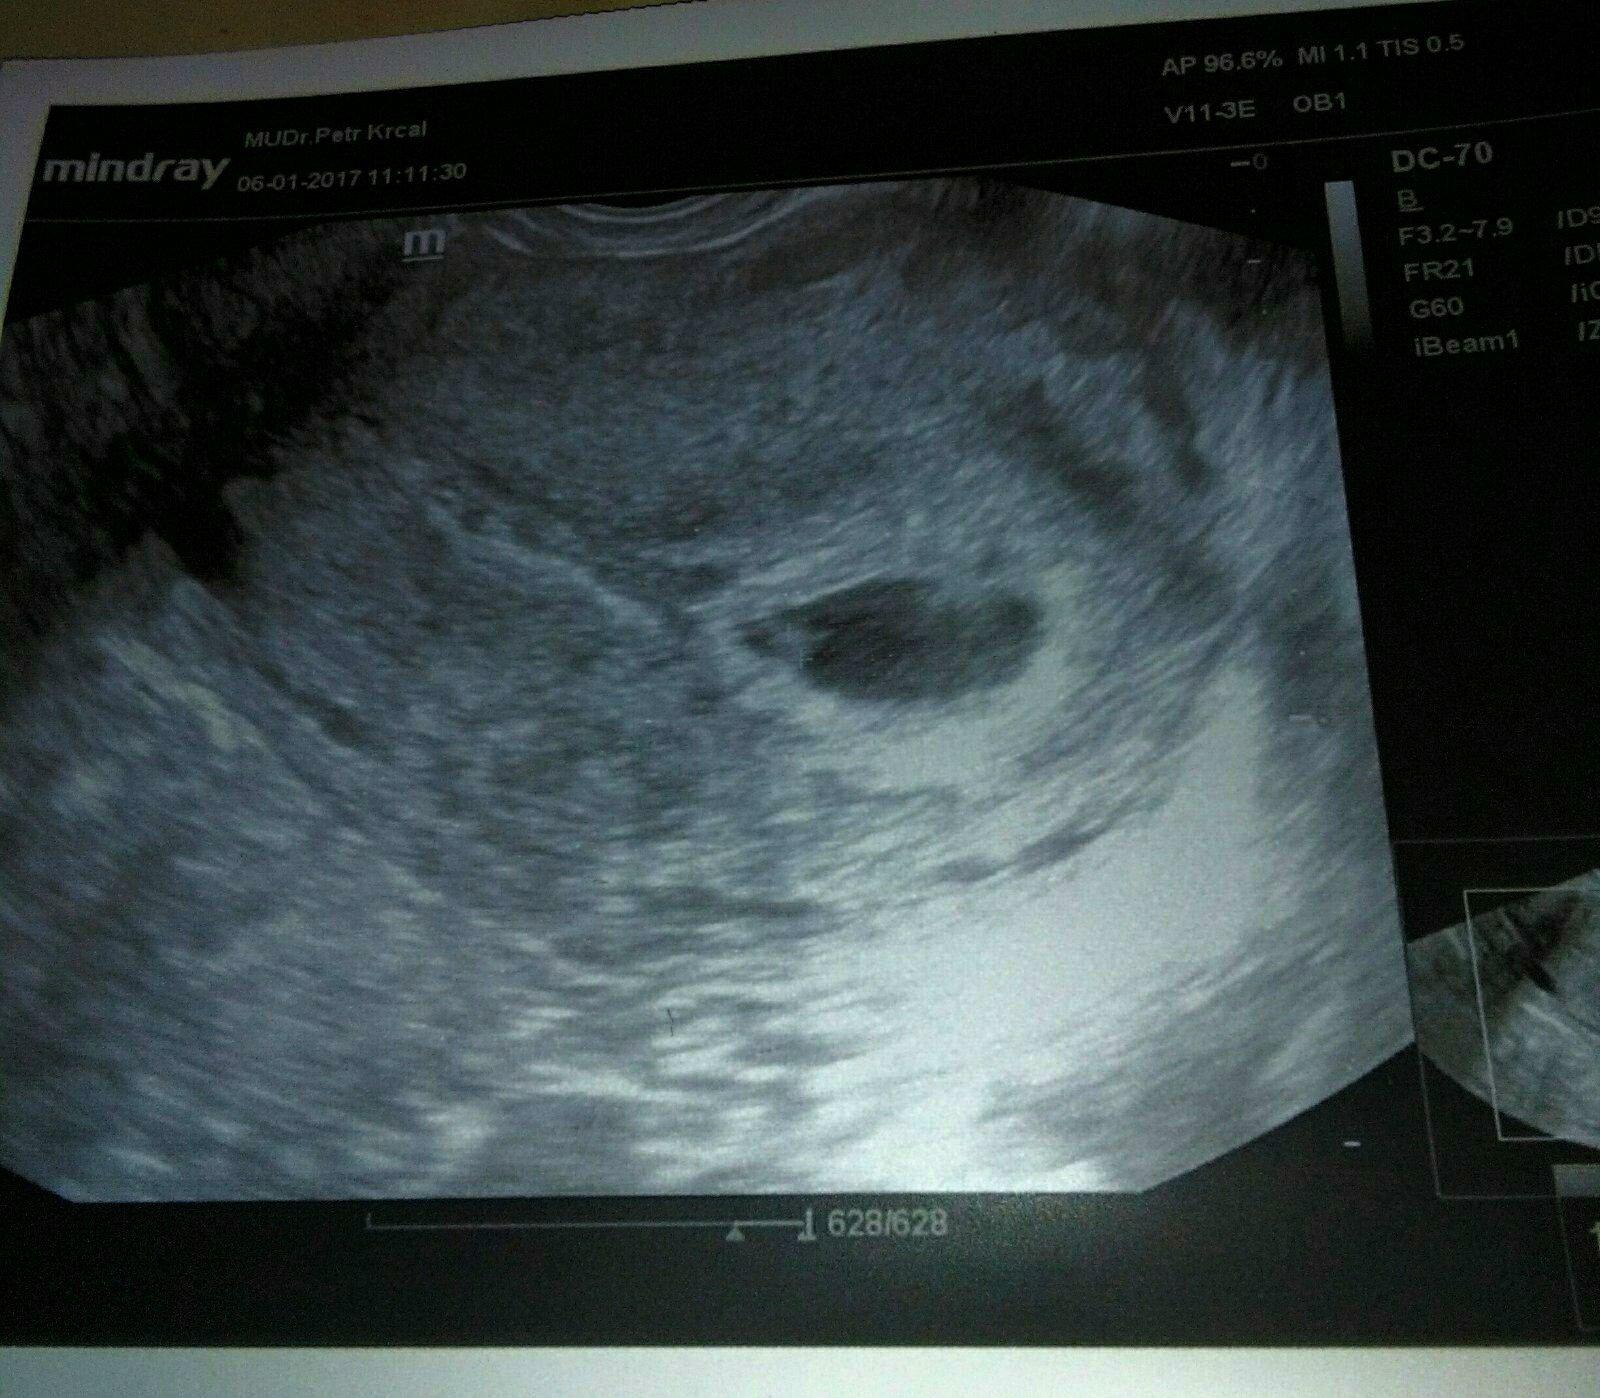

@zdenule23 tak já si nebyla jistá.já mela na utz naposledy tohle a to jsem byla v 5. týdnu s ms v 7.týdnu.

@zdenule23 v létě když jsem měla ZT tak to vypadalo v 5 týdnu takto a mělo to jen asi 6 mm, ted v 5.týdnu to má 2,4 cm a prý tehdy už bylo vidět, ze není něco v pořádku podle té bubliby a ted prý je to lepší než čekal a ze to odpovídá podle utz jak to má být. Tak snad příští pátek bude vše OK a bude i srdíčko, tehdy se ani nevyvinulo, prý tam nebyl ten terčík, co tam má být, ze kterého pak se vyvíjí srdíčko a ted tam naštěstí je.

@zdenule23 zapomněla jsem.přidat foto, jak jsem psala, že to vypadalo jinak v tom létě. Když kouknes na oba utz ten rozdíl je vidět. Tenhle je ten z léta.Také 5.tt.